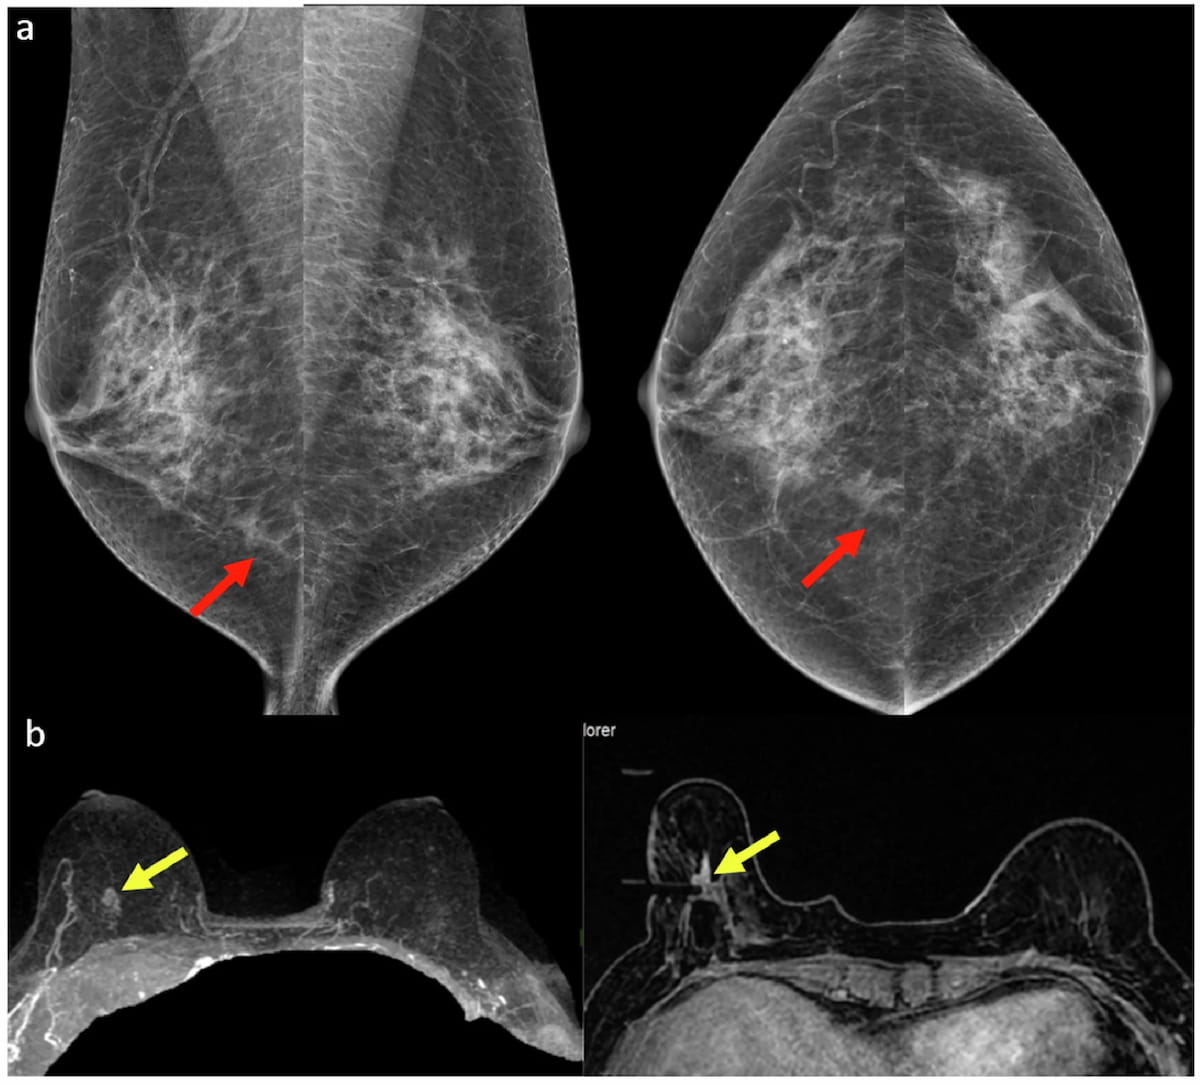

While dynamic contrast enhanced breast MRI may help reduce biopsies for suspicious calcifications on mammograms, quantitative MRI features and diffusion-weighted imaging (DWI) may not provide additional diagnostic benefit in these cases, according to a new study.